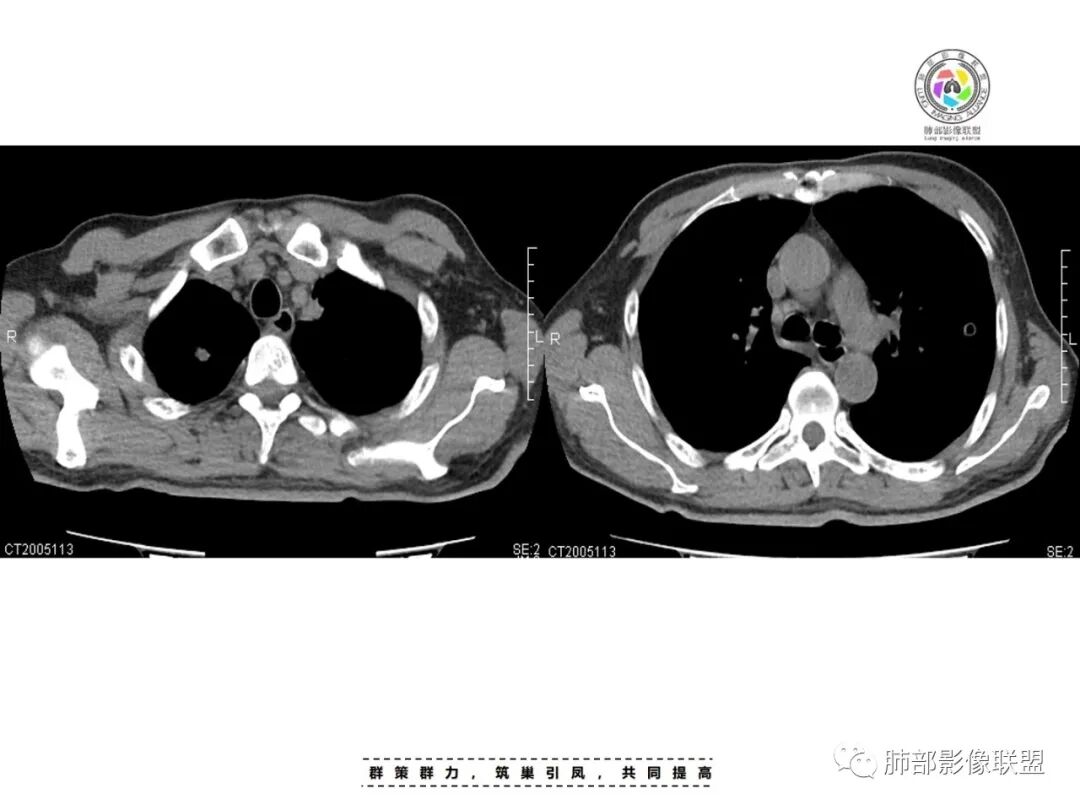

李:双肺多发结节,部分空洞,胸膜下为主,考虑血源性,治疗后好转,如果抗炎好转,考虑化脓菌栓,肺克或金葡,如激素治疗后考虑gpa亚东:双肺多发结节,部分见空洞,与血管关系紧密,考虑感染性病变,短期内变化快,糖尿病史,金葡,肺克?王秀仙:糖尿病基础上伴发的多发结节,部分空洞,四大金刚金毛结克,首选肺克琦遇:糖尿病四大金刚里按病史只有金葡和肺克符合,病灶特点,胸膜下为主,病灶偏少,有不干净空洞,肝功无异常,金葡可能性大!大雄:但是没有发热 小强:糖尿病史,胸膜下,6天空洞增大,金葡可能,肺克一般进展后有融合大片改变,这个没有,但是金葡临床症状更重,这个也看不出来崔少钢:中年男性,血糖控制不良,感染指标高。影像:双肺多发的结节、空洞,分布比较随机,考虑肺克。病变变化不够快,囊张力不够高,感觉不像金葡。大雄:血流感染的金葡 与肺克影像上有重叠,不一定好区分肺克炎性指标(PCT)可以高的更明显金葡血流感染一般有可追寻的来源,比如皮损,软组织脓肿,骨髓炎,心内膜炎等肺克一般是来源肠道,经门脉系统入肝,形成肉眼可见的肝脓肿或者不可见的隐匿性微脓肿,再经肝静脉回流→下腔静脉→右心→肺动脉→肺内播散张小兵:糖尿病基础,胸膜下多发结节伴空洞形成,这么大的空洞结节无播散,排除结核。肉芽肿性多血管炎,一般累及支气管,引起支气管狭窄,也可排除,倾向肺克,鉴别金葡。流心明智:男性,51岁,以咳嗽、咳痰、气喘3天。既往糖尿病10年。血常规wBC及中性比、CRP、PCT均升高。CT示:双肺多发结节、小斑片影,胸膜下多,大部分实性、部分伴空洞,大部分类圆形、部分呈楔形,部分病灶可见滋养血管征,治疗后逐渐吸收。考虑:感染性病变,SPE,金葡>肺克,鉴别隐球、TB等。

其次看肺克雷伯杆菌,肺克易肠道入血,糖尿病病史始终是个危险因素,受凉可能暂时影响到糖尿病患者的免疫力,以此作为肺克发病的原因,似乎可以解释,但是患者体温不高,仍是一个存有疑惑的地方。

影像学表现:a 气道来源分布,多在一侧上肺或双下肺后基底段,实变病灶无支气管充气征,实变外支气管壁增厚,病灶早期就可见坏死空洞,因渗出物粘稠密度较大,常叶间裂下坠,有膨胀感。b 血源性病灶位于胸膜下或沿支气管走形,病灶内见小空洞,易伴发肝脓肿。

(为什么糖尿病患者容易患肝脓肿、肺克?糖尿病或者血糖控制不良的患者,肝枯否细胞的吞噬能力下降,吞噬后无法正常产生次氯酸清除细菌,造成异位肠菌滞留肝脏,这些肠道细菌中肺克拥有最大的荚膜且毒力和侵袭力俱强,故糖尿病患者容易发生肝脓肿,而肝脓肿大多数为肺克)。